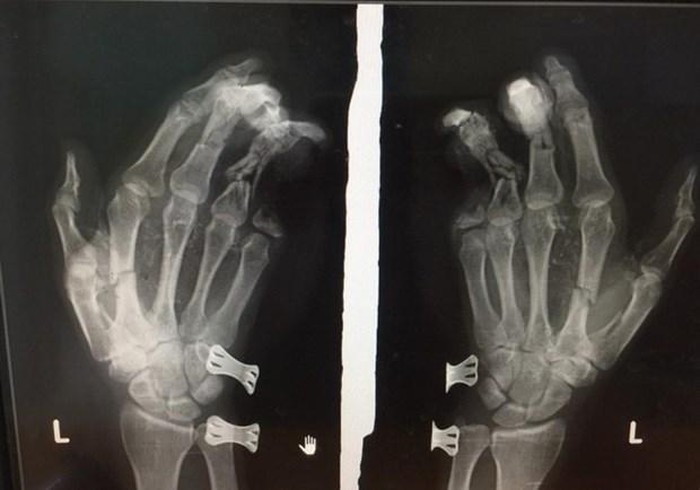

Phim chụp bàn tay của nam thanh niên bị tổn thương do điện thoại phát nổ.

Hậu quả, bàn tay trái của anh Duy dập nát, tổn thương nặng và ngón út bị cụt mất 2 đốt. Tại Bệnh viện Đa khoa II Lâm Đồng anh Duy được sơ cứu, chụp phim và đưa vào phòng phẫu thuật khâu lại viết thương.

Theo lãnh đạo Bệnh viện Đa khoa II Lâm Đồng, ngón út của nạn nhân bị mất hai đốt không thể phẫu thuật ghép nối. Đây là bài học cảnh tỉnh cho những người vừa sử dụng điện thoại vừa sạc pin./.